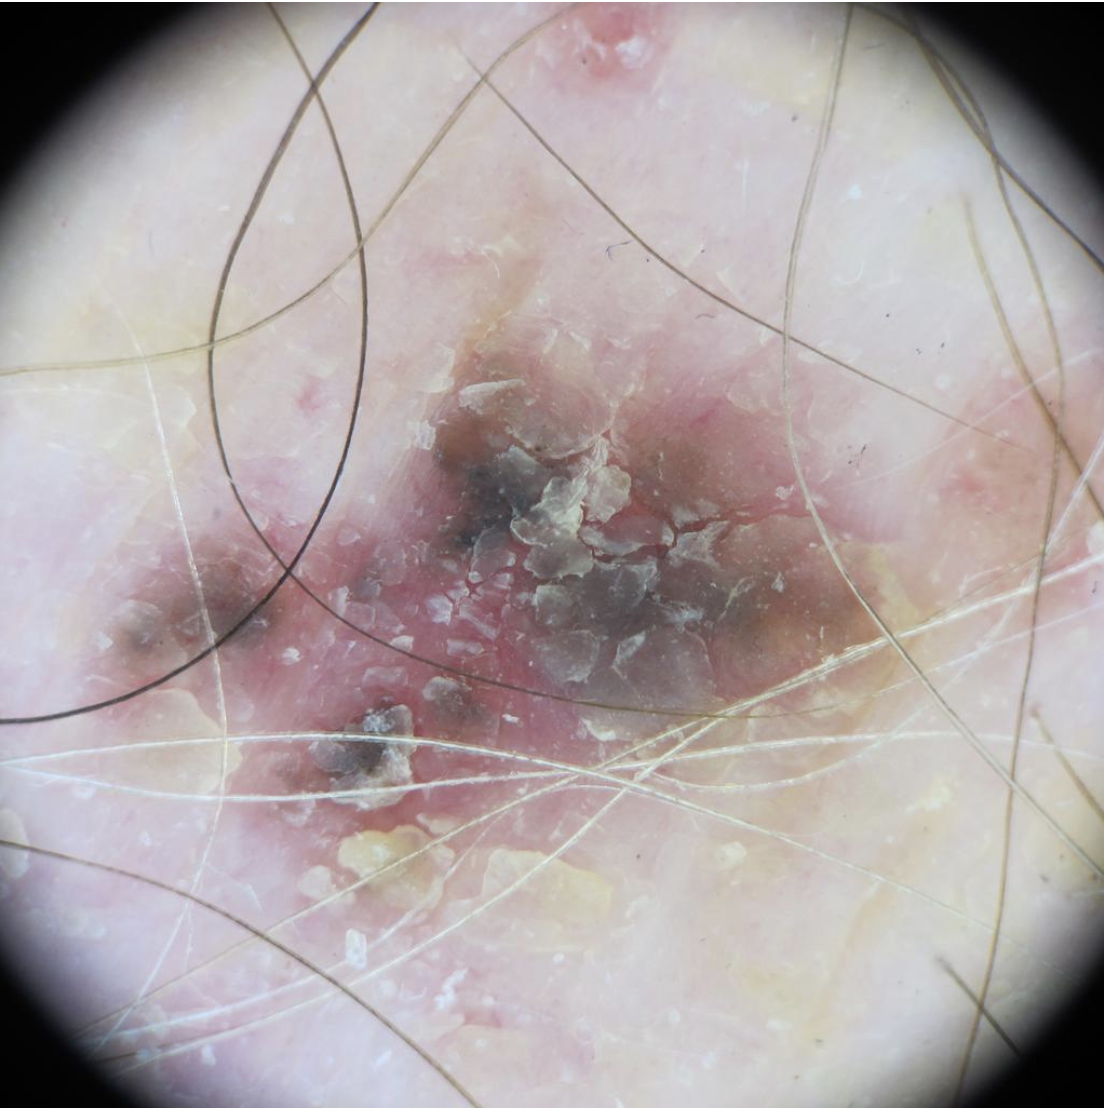

Squamous Cell Carcinoma (SCC) Photos

Squamous cell carcinoma on the nose. Photo: International Skin Imaging Collaboration at isic-archive.com

Squamous cell carcinoma on the head. Photo: International Skin Imaging Collaboration at isic-archive.com

Squamous cell carcinoma on the neck. Photo: International Skin Imaging Collaboration at isic-archive.com

An elevated growth with a central depression that occasionally bleeds. It may rapidly increase in size. (SCC)